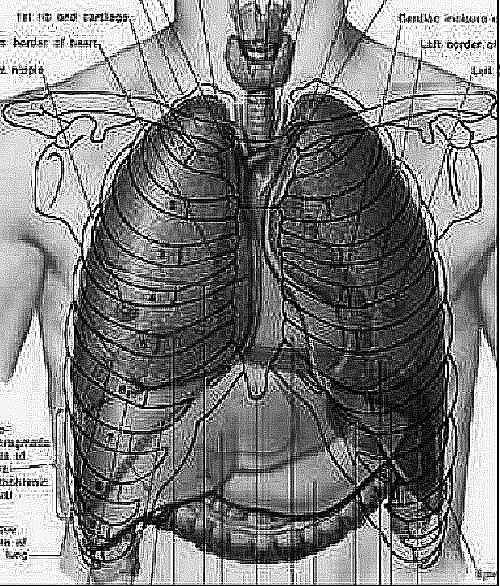

La paroi de la

cage thoracique comporte en des côtes et os sternum

en avant et la colone vertebrale en arriere et à

inferieure c'est le diaphragme . Sa contenue est les

deux poumon et le mediastin au milieur |

Les deux poumon sont entoure par la

plevre parietal et de plevre visceral . Poumon droit

est divise en trois lobe , superieur , moyen et

inferieure par des cloisons interlobaires de plevre

visceral droit : grand scissure et petite scissure .

Poumon gauche est en divise en deux lobe superieur

et inferieure par grand scissure gauche |